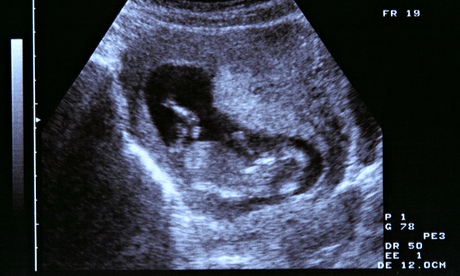

ultrasound image

The human rights commission is seeking a change in the law that would increase access to abortion for women in Northern Ireland. Photograph: Alamy